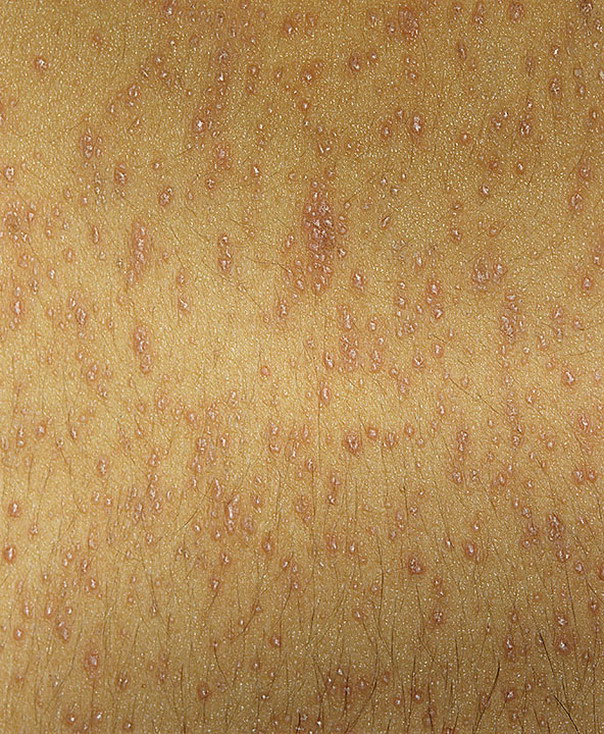

Фото Красного Плоского

Фото Красного Плоского 103 фото